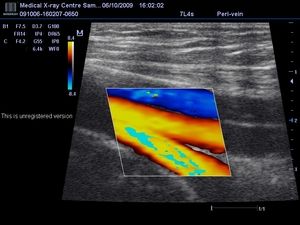

Савремени уређаји за дуплекс скенирање омогућавају добијање информација о стању њихових пловила не само у „стварном времену“, већ и у облику колор слике, што омогућава да се са великом тачношћу утврди присуство или одсуство болести.

Информације добијене као резултат дијагнозе проучава лекар дијагностике ради било каквих патолошких промена на крвним судовима. Доплерски спектри и картограми у боји показују природу тона зидова крвних канала, као и показатеље отпорности периферних судова.